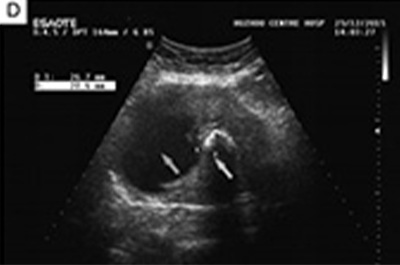

这项研究报告了1例59岁绝经后女性患子宫骨肉瘤并表现为恶性混合苗勒管肿瘤的罕见病例。通过MRI、超声检查、血清肿瘤标志物检测、手术及病理诊断等方式,对患者病情进行详细分析,并探讨了该疾病的相关特征和治疗方案。

结果发现,患者经手术和病理诊断,确诊为子宫骨肉瘤合并恶性混合苗勒管肿瘤,包含子宫内膜腺癌、软组织肉瘤和骨肉瘤成分,且存在淋巴结转移,分期为IIIC2期。